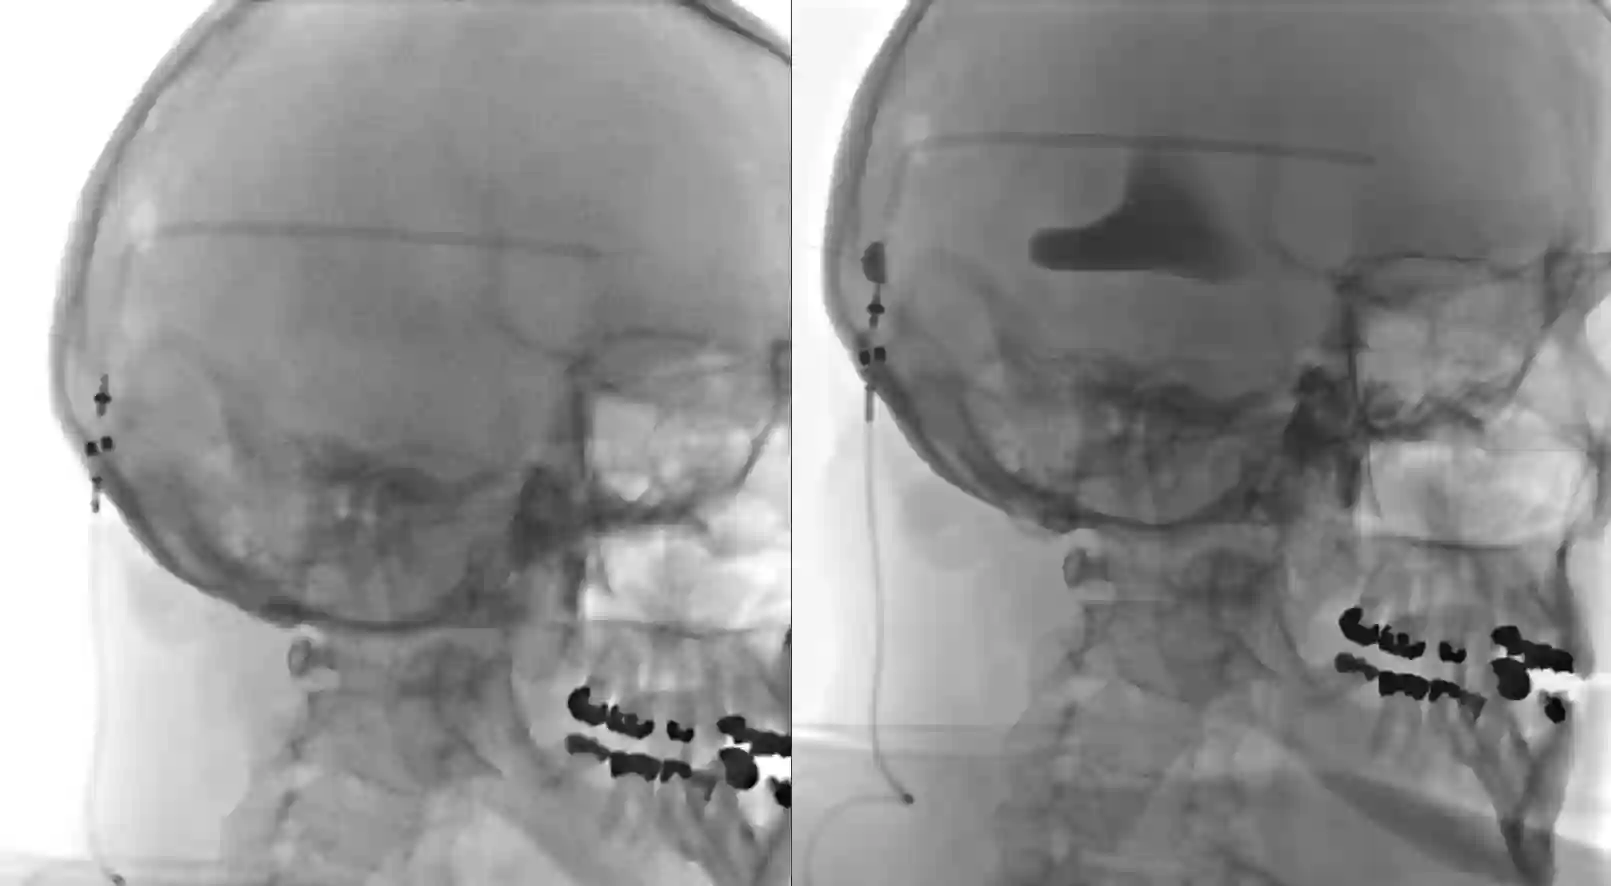

Shuntpunktion

Shuntpunktion mit Gabe von Kontrastmittel zur Überprüfung des proximalen Ventrikelkatheters.